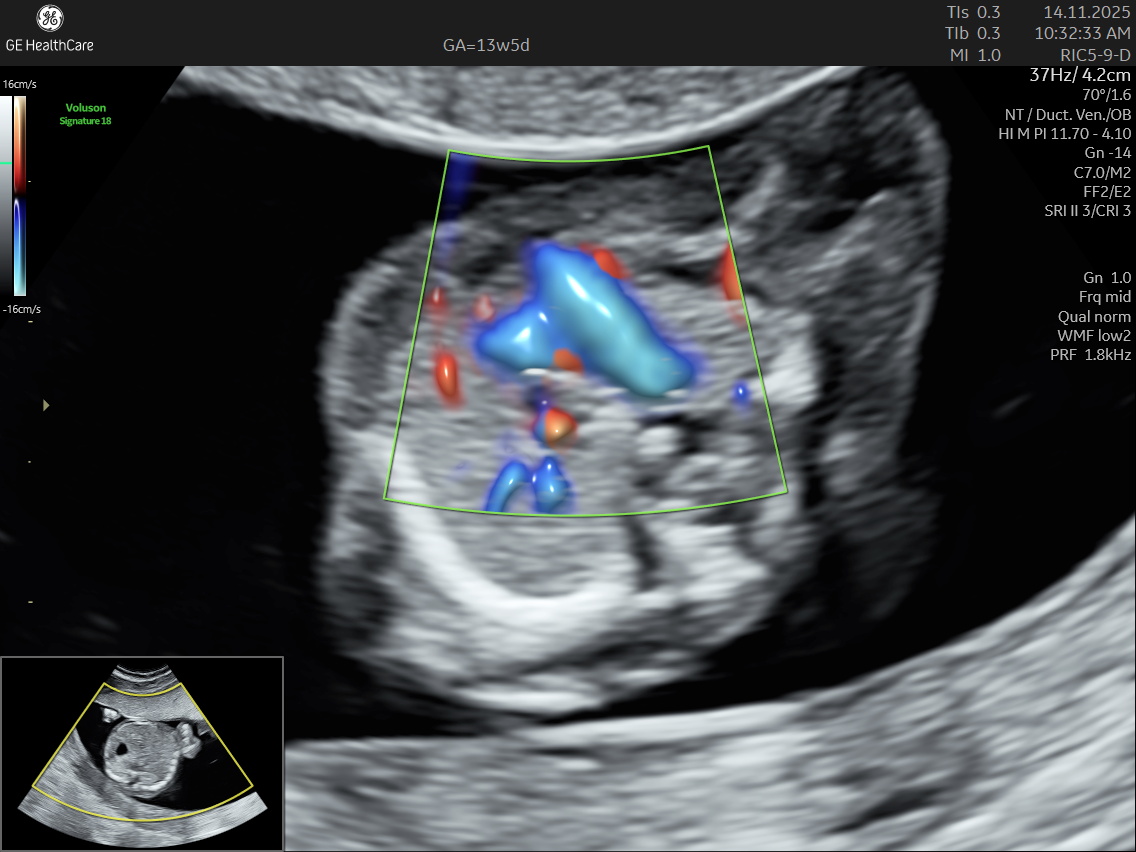

NESA Institute of Fetal Medicine offers specialized first-trimester screening for expectant parents, delivering high-precision NT scans between 12 to 13 weeks of pregnancy. Our experienced fetal medicine team ensures accurate risk assessment for chromosomal abnormalities, including Down syndrome, Edwards syndrome, and Patau syndrome.

The NT scan is a non-invasive ultrasound examination conducted in the first trimester (12–13 weeks). It measures the nuchal translucency (the fluid at the back of the fetus’s neck) and combines it with the maternal blood test for a detailed risk profile. NT Scan is an important early screening test for Down syndrome (Trisomy 21), Edwards syndrome (Trisomy 18), and Patau syndrome (Trisomy 13).

- Congenital heart defects, which are among the most common physical birth defects, including septal defects and tetralogy of Fallot.

Although the NT scan is mainly a screening tool and not diagnostic on its own, it can identify about 50% of major fetal abnormalities when combined with other assessments like blood tests and detailed ultrasound. The scan also helps to screen some basic anatomical structures during the first trimester, especially the fetal heart anatomy, brain, face, spine, stomach, abdominal wall, kidneys, bladder, and extremities to varying degrees depending on gestational age and maternal factors.